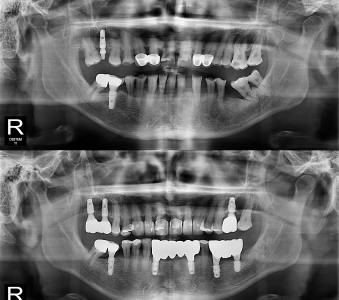

오스템 임플란트 프리미엄 BA 등급 사용

같은 오스템이라도 등급이 다릅니다. 더 빠른 골유착을 위해 프리미엄 등급을 사용합니다.

결과로 증명합니다.

국제모아치과의

실제 임상 증례